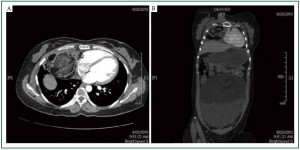

Ultrasound (USG) abdomen showed large encapsulated cystic mass lesion measuring approximately 22 cm × 20 cm × 10 cm seen in the pelvis and extending in to the abdomen. Her blood parameters were within normal limits so was her Alfa-feto protein (AFP), CA 125 and Beta-human chorionic gonadotropin (b-HCG) values. Further evaluating, Computerised Tomography of chest and abdomen (Figure 2A, 2B) revealed a well encapsulated solid-cystic mass lesion 9 cm × 6.5 cm × 6.6 cm in the anterior mediastinum in the right paracardiac region with smooth thick wall and area of focal calcification. The contents of the cystic lesion are hetrogenous with predominant fat density with no signs of chest wall or pericardial invasion suggesting of mediastinal mature teratoma and large heterogeneous, sharply marginated cystic lesion arising from the left ovary.

Figure 2. A: CT scan Axial view of chest at level of cardia showing a well defined cystic mass in right para cardia with smooth thick wall and area of focal calcification. The cystic content are heterogeneous with predominant fat density; B: Coronal section CT scan showing large cystic lesion in pelvis and lower abdomen and mass lesion in the mediastinum.